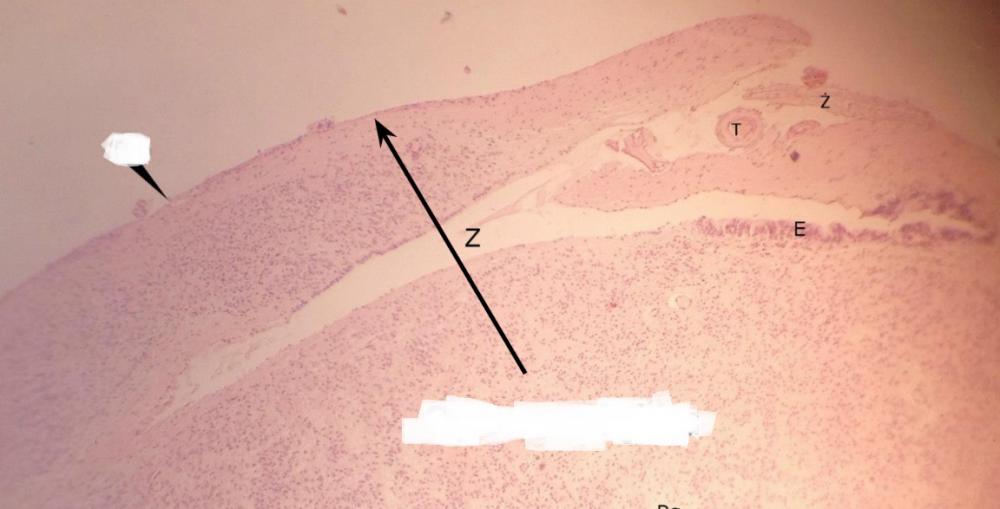

torebka łącznotkankowa (nadnercze)

Pytanie 272

warstwa kłębkowata kory (nadnercze)

Pytanie 273

warstwa pasmowata kory (nadnercze)

Pytanie 274

warstwa siatkowata kory (nadnercze)

Pytanie 275

naczynie zatokowe - małe, podłużne, białe pasmo (nadnercze)

Pytanie 276

żyła nadnerczowa (nadnercze)

Pytanie 277

rdzeń - z feochromocytami (nadnercze)